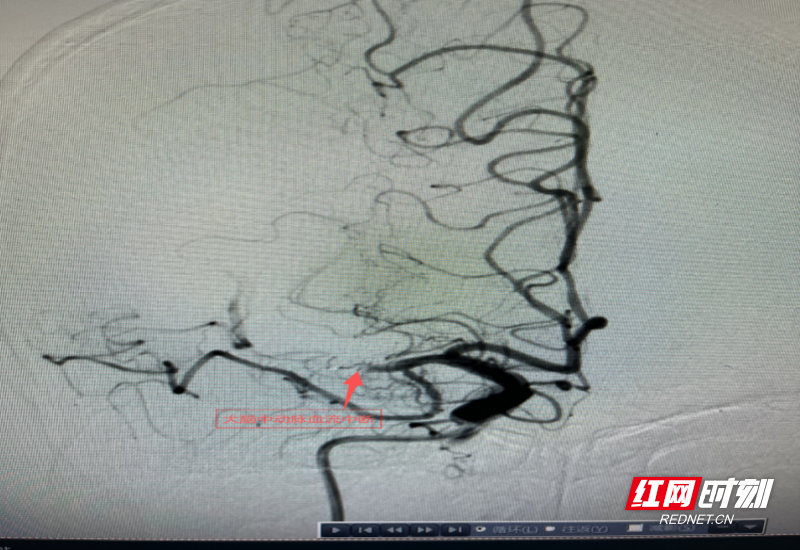

术中造影显示,患者右侧大脑中动脉主干完全闭塞,若不能及时开通血管,将引发大面积脑梗死,致死致残风险极高。张扬龙沉着操作,精准置入取栓支架,成功取出堵塞血管的血栓,并对狭窄血管进行球囊扩张塑形。整个手术不到一小时便顺利完成,堵塞的血管成功开通,脑部血流恢复正常。